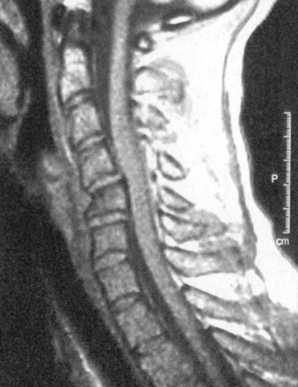

Ценную информацию о состоянии вывихнутых позвонков и спинного мозга дает

МРТ (рис. 2.6, 2.7). МРТ позволяет определить наличие зон ишемии в спинном

мозге (рис. 2.8, 2.9), состояние ликвородинамики (рис. 2.10).

|

Рис. 2.6. Переломо-вывих скользящий

C5-C6, позвонков со смещением тела С5 кзади с грубой компрессией спинного

мозга на данном уровне |

Рис. 2.7. Переломо-вывих скользящий C6-C7 позвонков с компрессией

спинного мозга на данном уровне

Рис. 2.8. Компрессионный перелом с подвывихом кзади С4 позвонка

с зоной ишемии спинного мозга

Рис. 2.9. Вывих С4-С5, позвонков с зоной ишемии спинного мозга

Рис. 2.10. Компрессионный перелом С6 позвонка со смещением его

кзади

и нарушением ликвороциркуляции на данном уровне